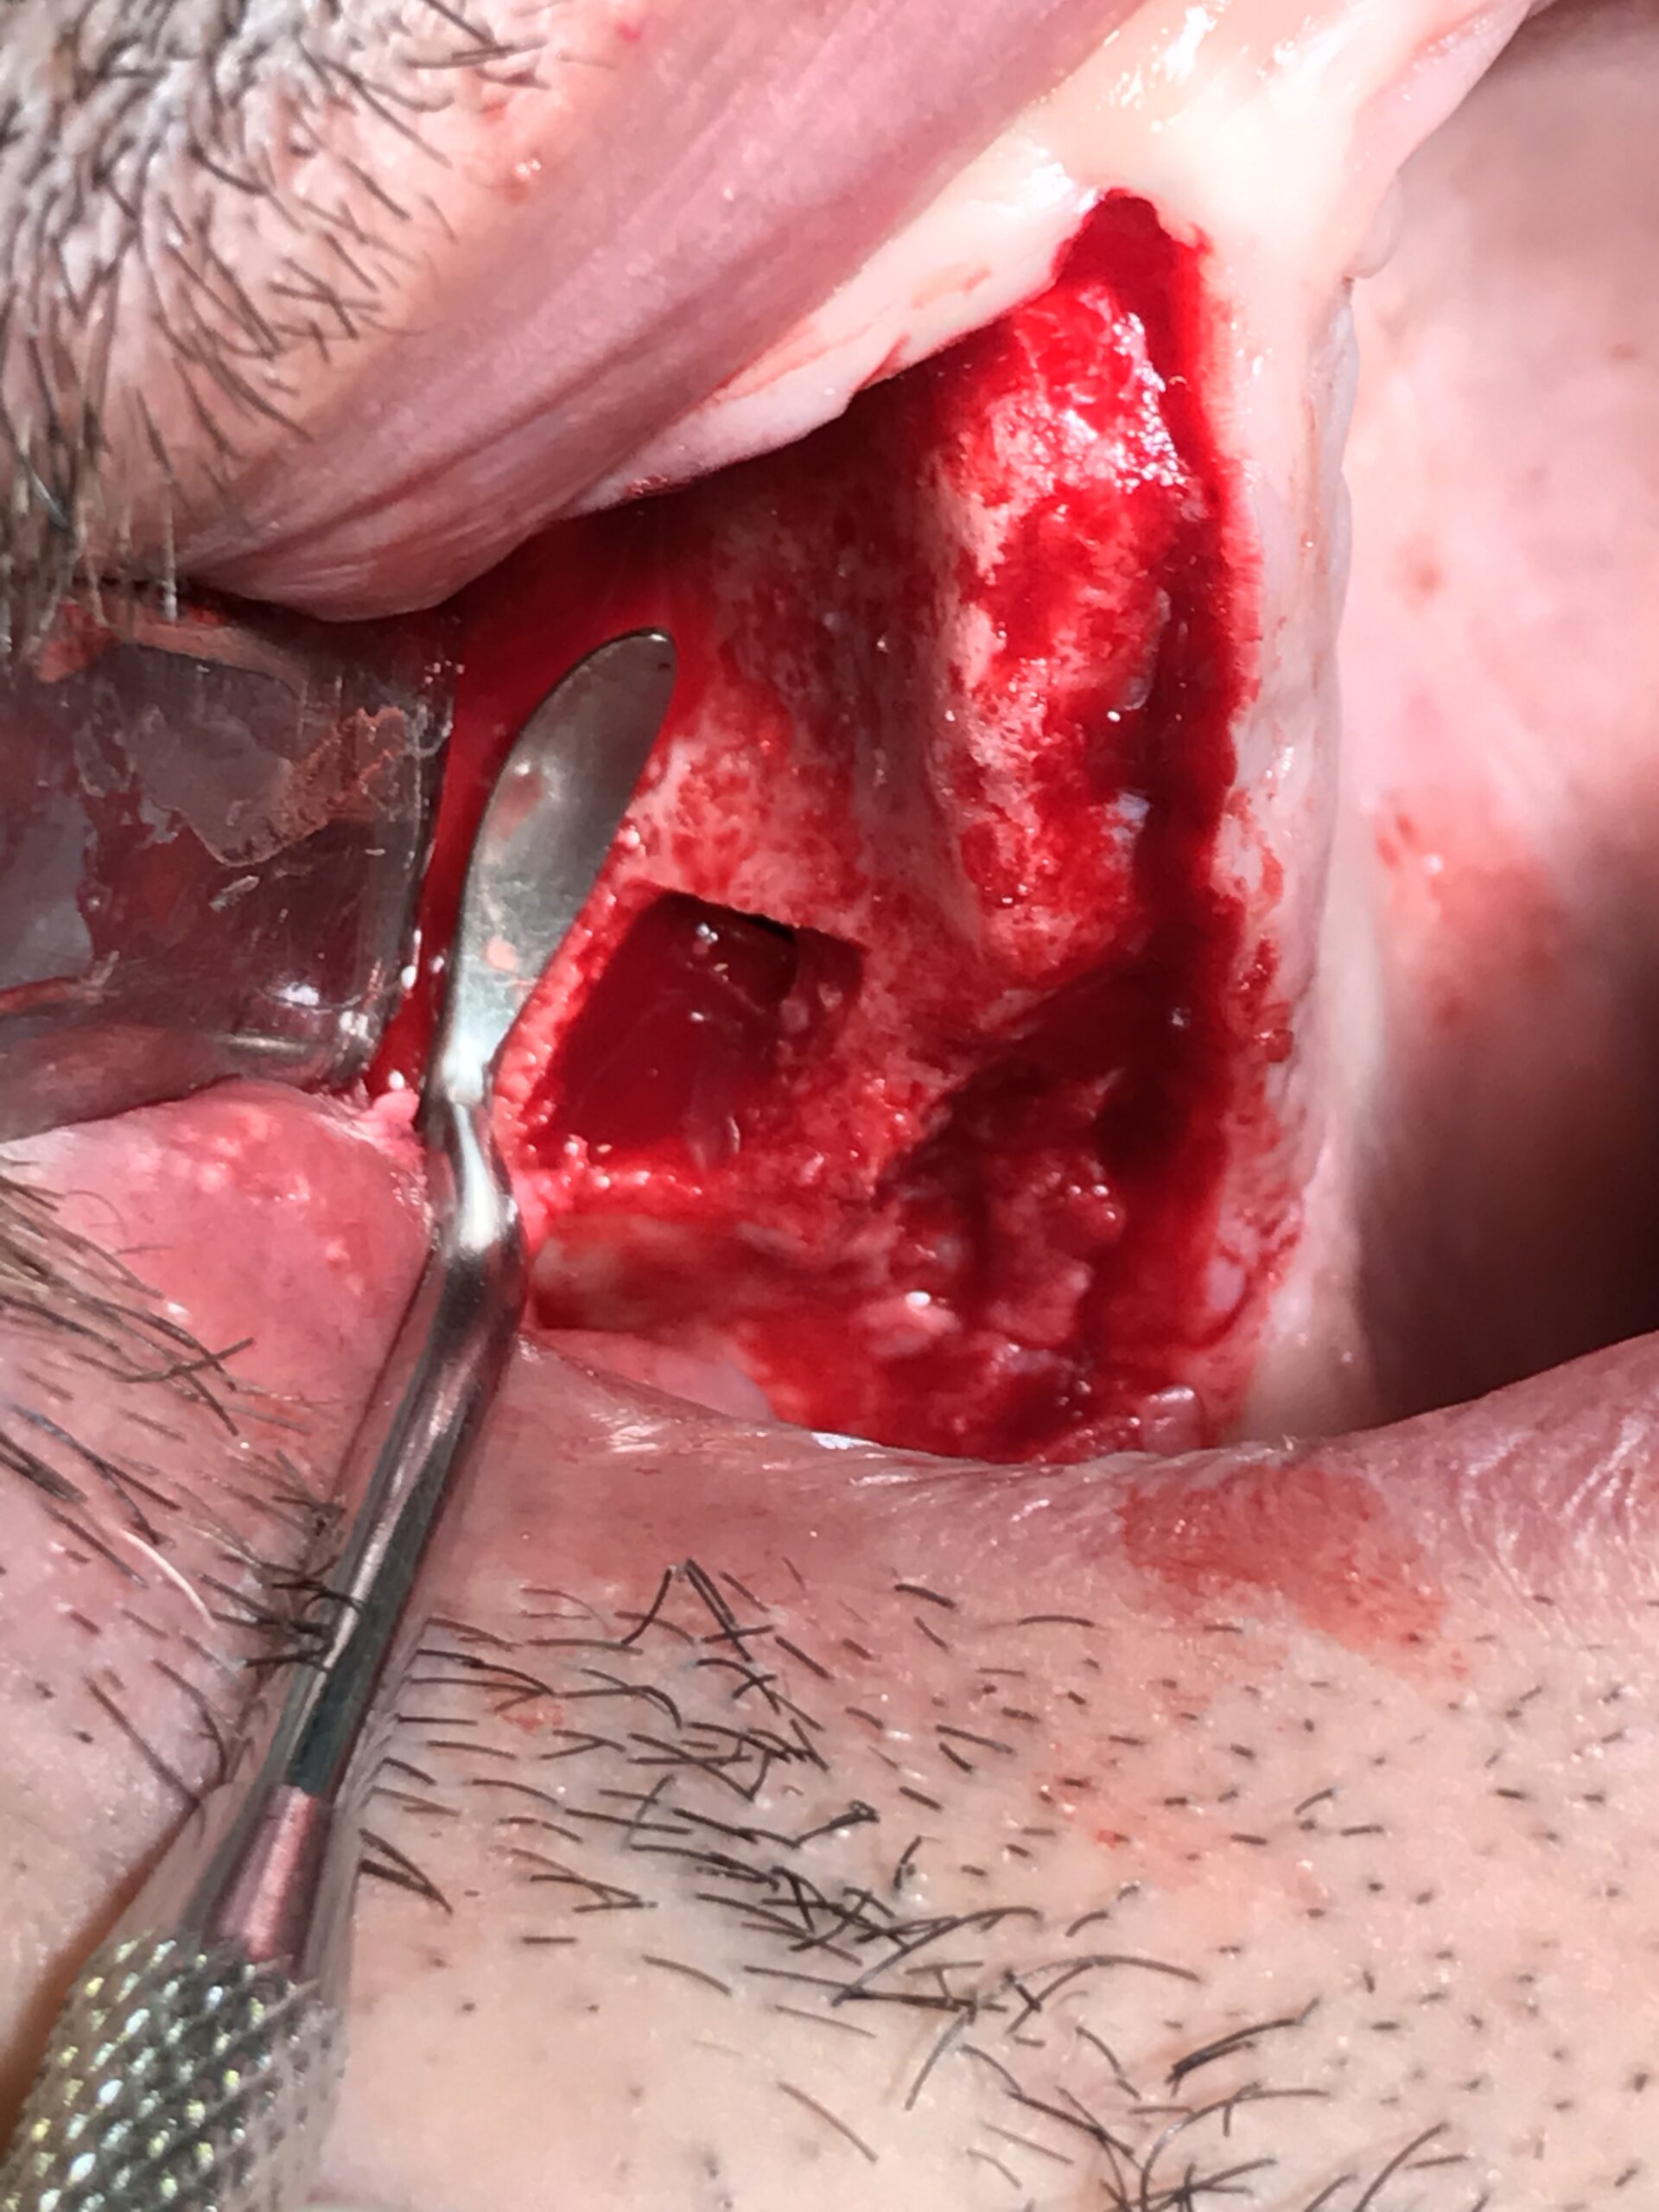

Medico chirurgo,specialista chirurgia maxillo facciale,specialista odontostomatologia,prof. Implantologia Università di Genova,propone consulenze/collaborazione presso Colleghi in chirurgia orale ed implantare ogni livello:sinus lift,all on four,cisti,inclusi,disinclusioni ortodontiche,apicectomie,ecc. protesi. Attrezzatura propria. Nord Italia. Tel. 3932000084.